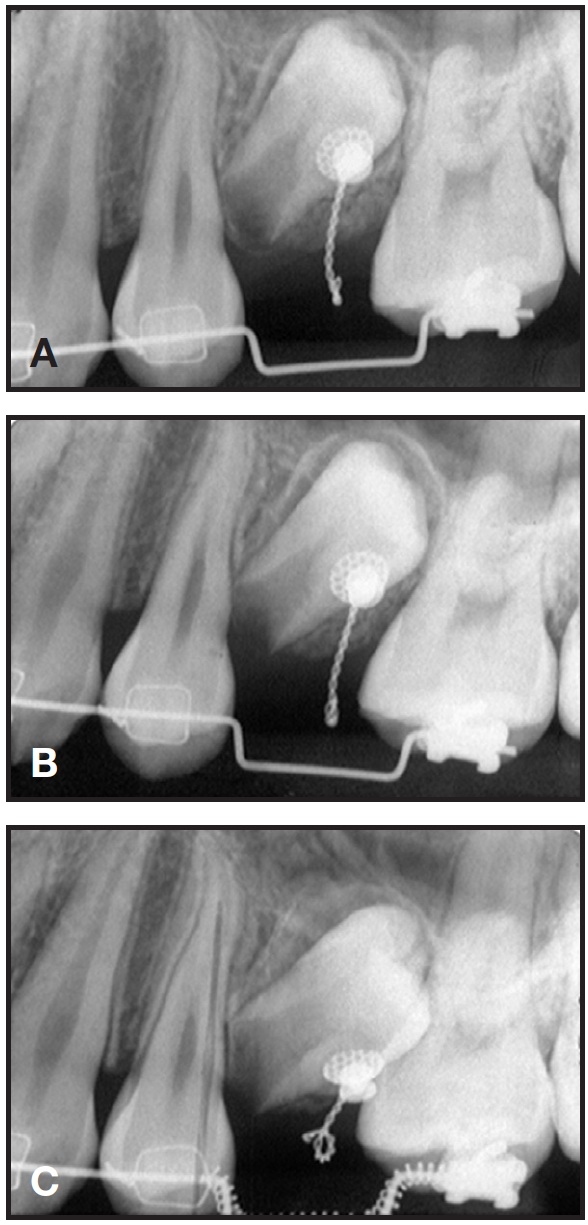

After seven days of healing, orthodontic treatment was resumed. Traction was applied to the twisted stainless steel ligature to bring about full eruption of the tooth. Since the distance between the ligature wire and the main archwire was too short to apply force, a stepdown bend was made in the archwire, and an open-coil spring was inserted between the first molar and first premolar to open and maintain adequate space for the second premolar (Fig. 3). The progress of impacted tooth movement was evaluated monthly (Fig. 4). After three months, to produce more clockwise rotation of the impacted tooth, the metal button was replaced by a minitube and an .016" × .022" TMA*** auxiliary wire was bent and attached (Fig. 5). Three months later, the wire was activated to create an additional rotational moment (Fig. 6).

Fig. 5 Minitube bonded to impacted premolar, and .016" × .022" TMA*** auxiliary wire bent and attached.

Fig. 6 A. Three months later, auxiliary wire activated to create additional rotational moment. B. After 11 months of treatment.